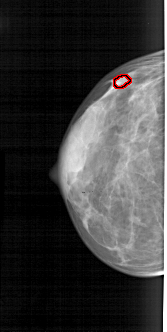

FILE: A_1841_1.LEFT_MLO.OVERLAY TOTAL_ABNORMALITIES 1 ABNORMALITY 1 LESION_TYPE CALCIFICATION TYPE PLEOMORPHIC DISTRIBUTION CLUSTERED ASSESSMENT 4 SUBTLETY 1 PATHOLOGY BENIGN TOTAL_OUTLINES 1 BOUNDARY |